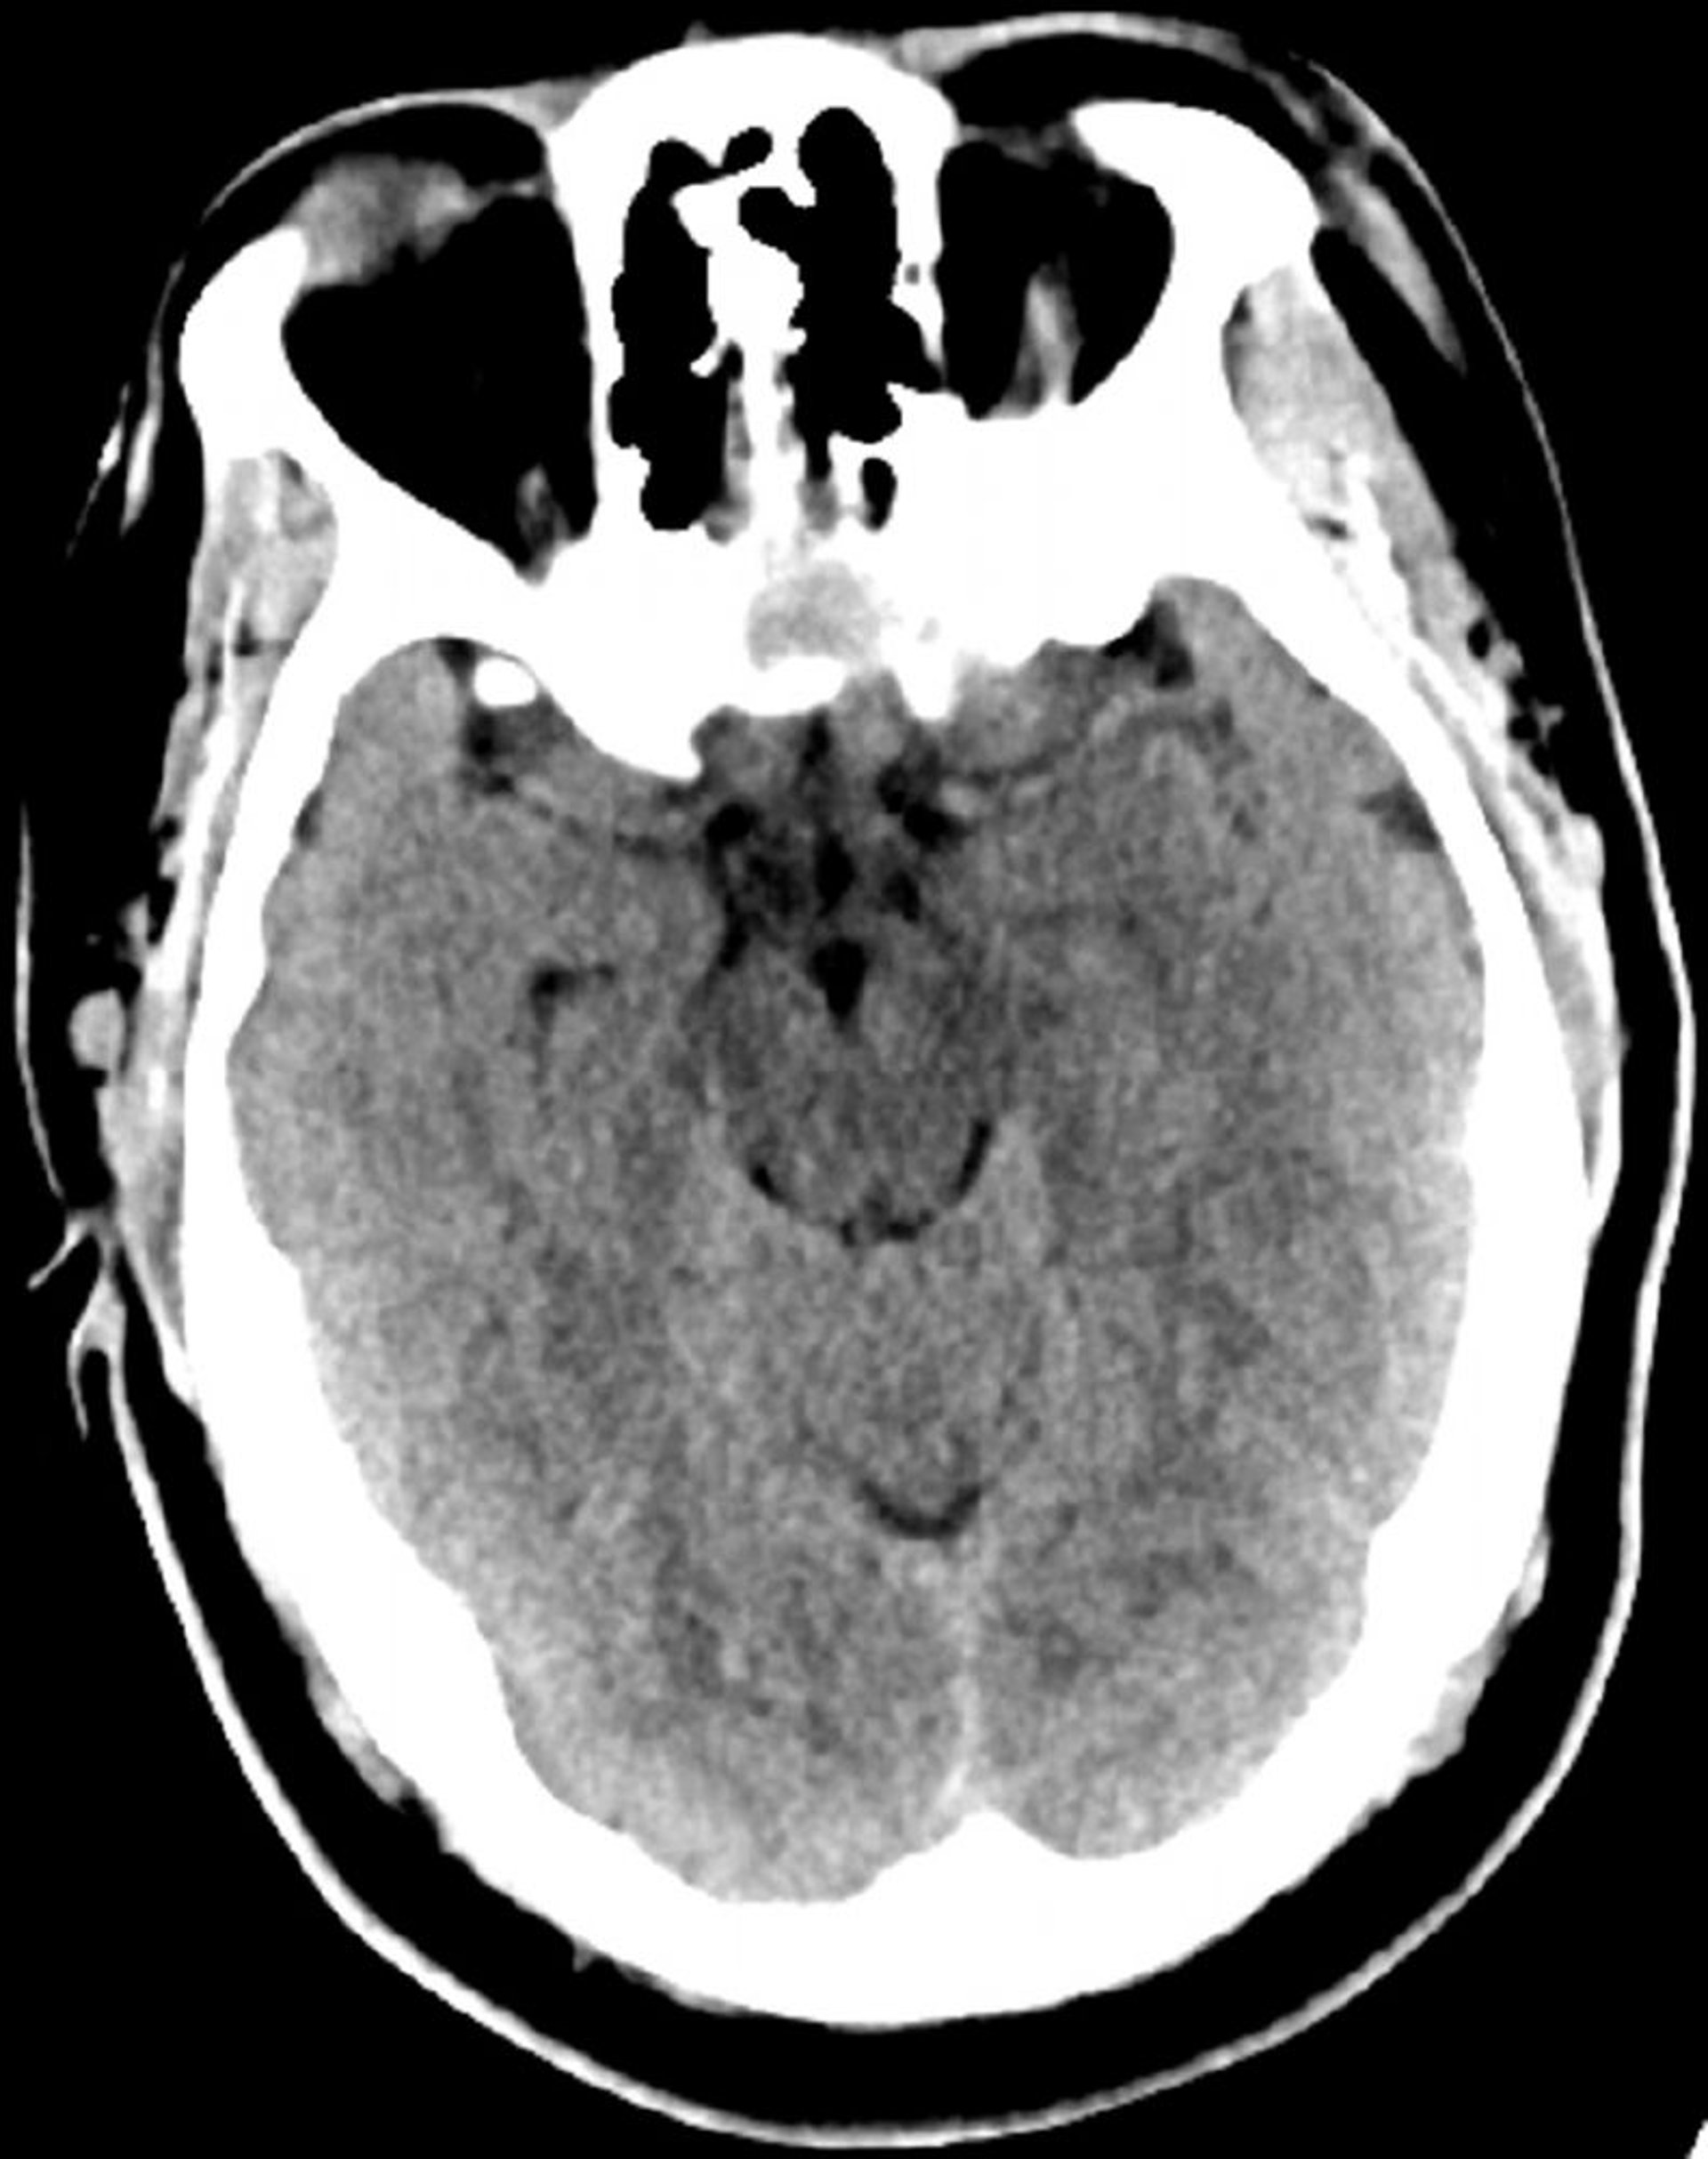

Normaler Kopf CT-Scan (Erwachsene, Alter 30) – Folie 6

Dieses Bild ist ein normaler CT-Scan des Kopfes eines jungen Erwachsenen im Alter von 30 Jahren. Es gibt keine intra- oder extraaxiale Flüssigkeit oder Blutung. Die grauweiße Unterscheidung bleibt erhalten. Ventrikuläre Größe und Sulcalmuster sind normal.